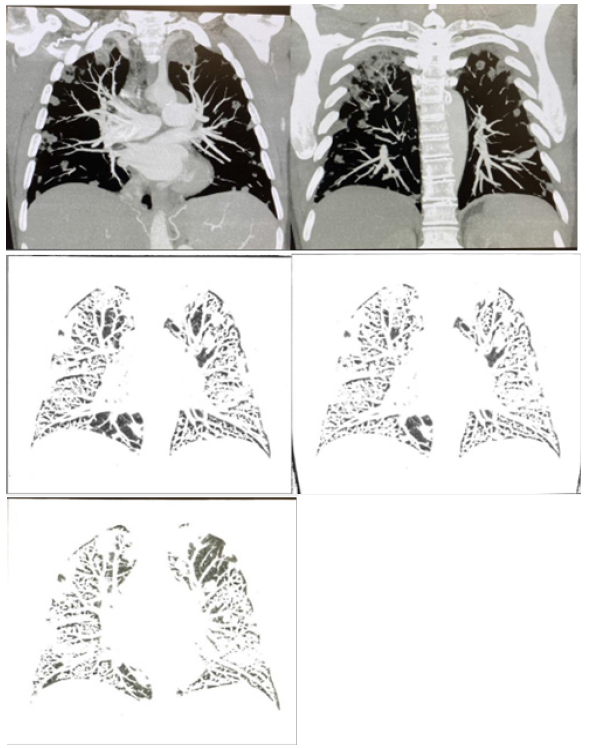

The patient was imaged with a chest CT with IV contrast as shown by Figure 1 and compared to his imaging from last week. He had a dilation of 4.0 cm of the main pulmonary artery and trace pericardial effusion. Imaging also found innumerable new predominantly peripheral cavitary nodules throughout both lungs, multiple enlarged mediastinal and hilar nodes, 4 cm cyst on the left kidney and mild degenerative changes of the thoracic spine.

Septic embolism is highly correlated with findings on CT and positron emission tomography (PET) imaging. A retrospective analysis of 20 patients found that there were bilateral pulmonary abnormalities in 90% of patients who had septic embolism, including: parenchymal opacities, nodular infiltrates, pleural effusion, and lymphadenopathy [23]. These clinical findings were present in CT imaging of the patient, specifically cavitary nodules, pulmonary artery dilation, trace pericardial effusion, and enlarged mediastinal and hilar lymph nodes.

Additionally, imaging of other body systems has been found to be a useful diagnostic tool and influential factor in treatment of septic embolism. Imaging of organs highly involved in the pathogenesis of septic embolism, such as the spleen, can be a confirmatory indication of the etiology [24]. Further, it has been found that spinal involvement of causative pathogens for septic embolism can change treatment priorities and objectives; in particular, a possible finding of spondylodiscitis may influence post interventional therapies [24]. Studies on the spine of our patient demonstrated mild degenerative changes as shown by Figure 1. Fortunately, these findings were not adequate to warrant concern. Nonetheless, imaging of the patient was an essential component of the diagnostic process that led to confirmation of septic embolism as well as produced findings useful in the management of the complication.